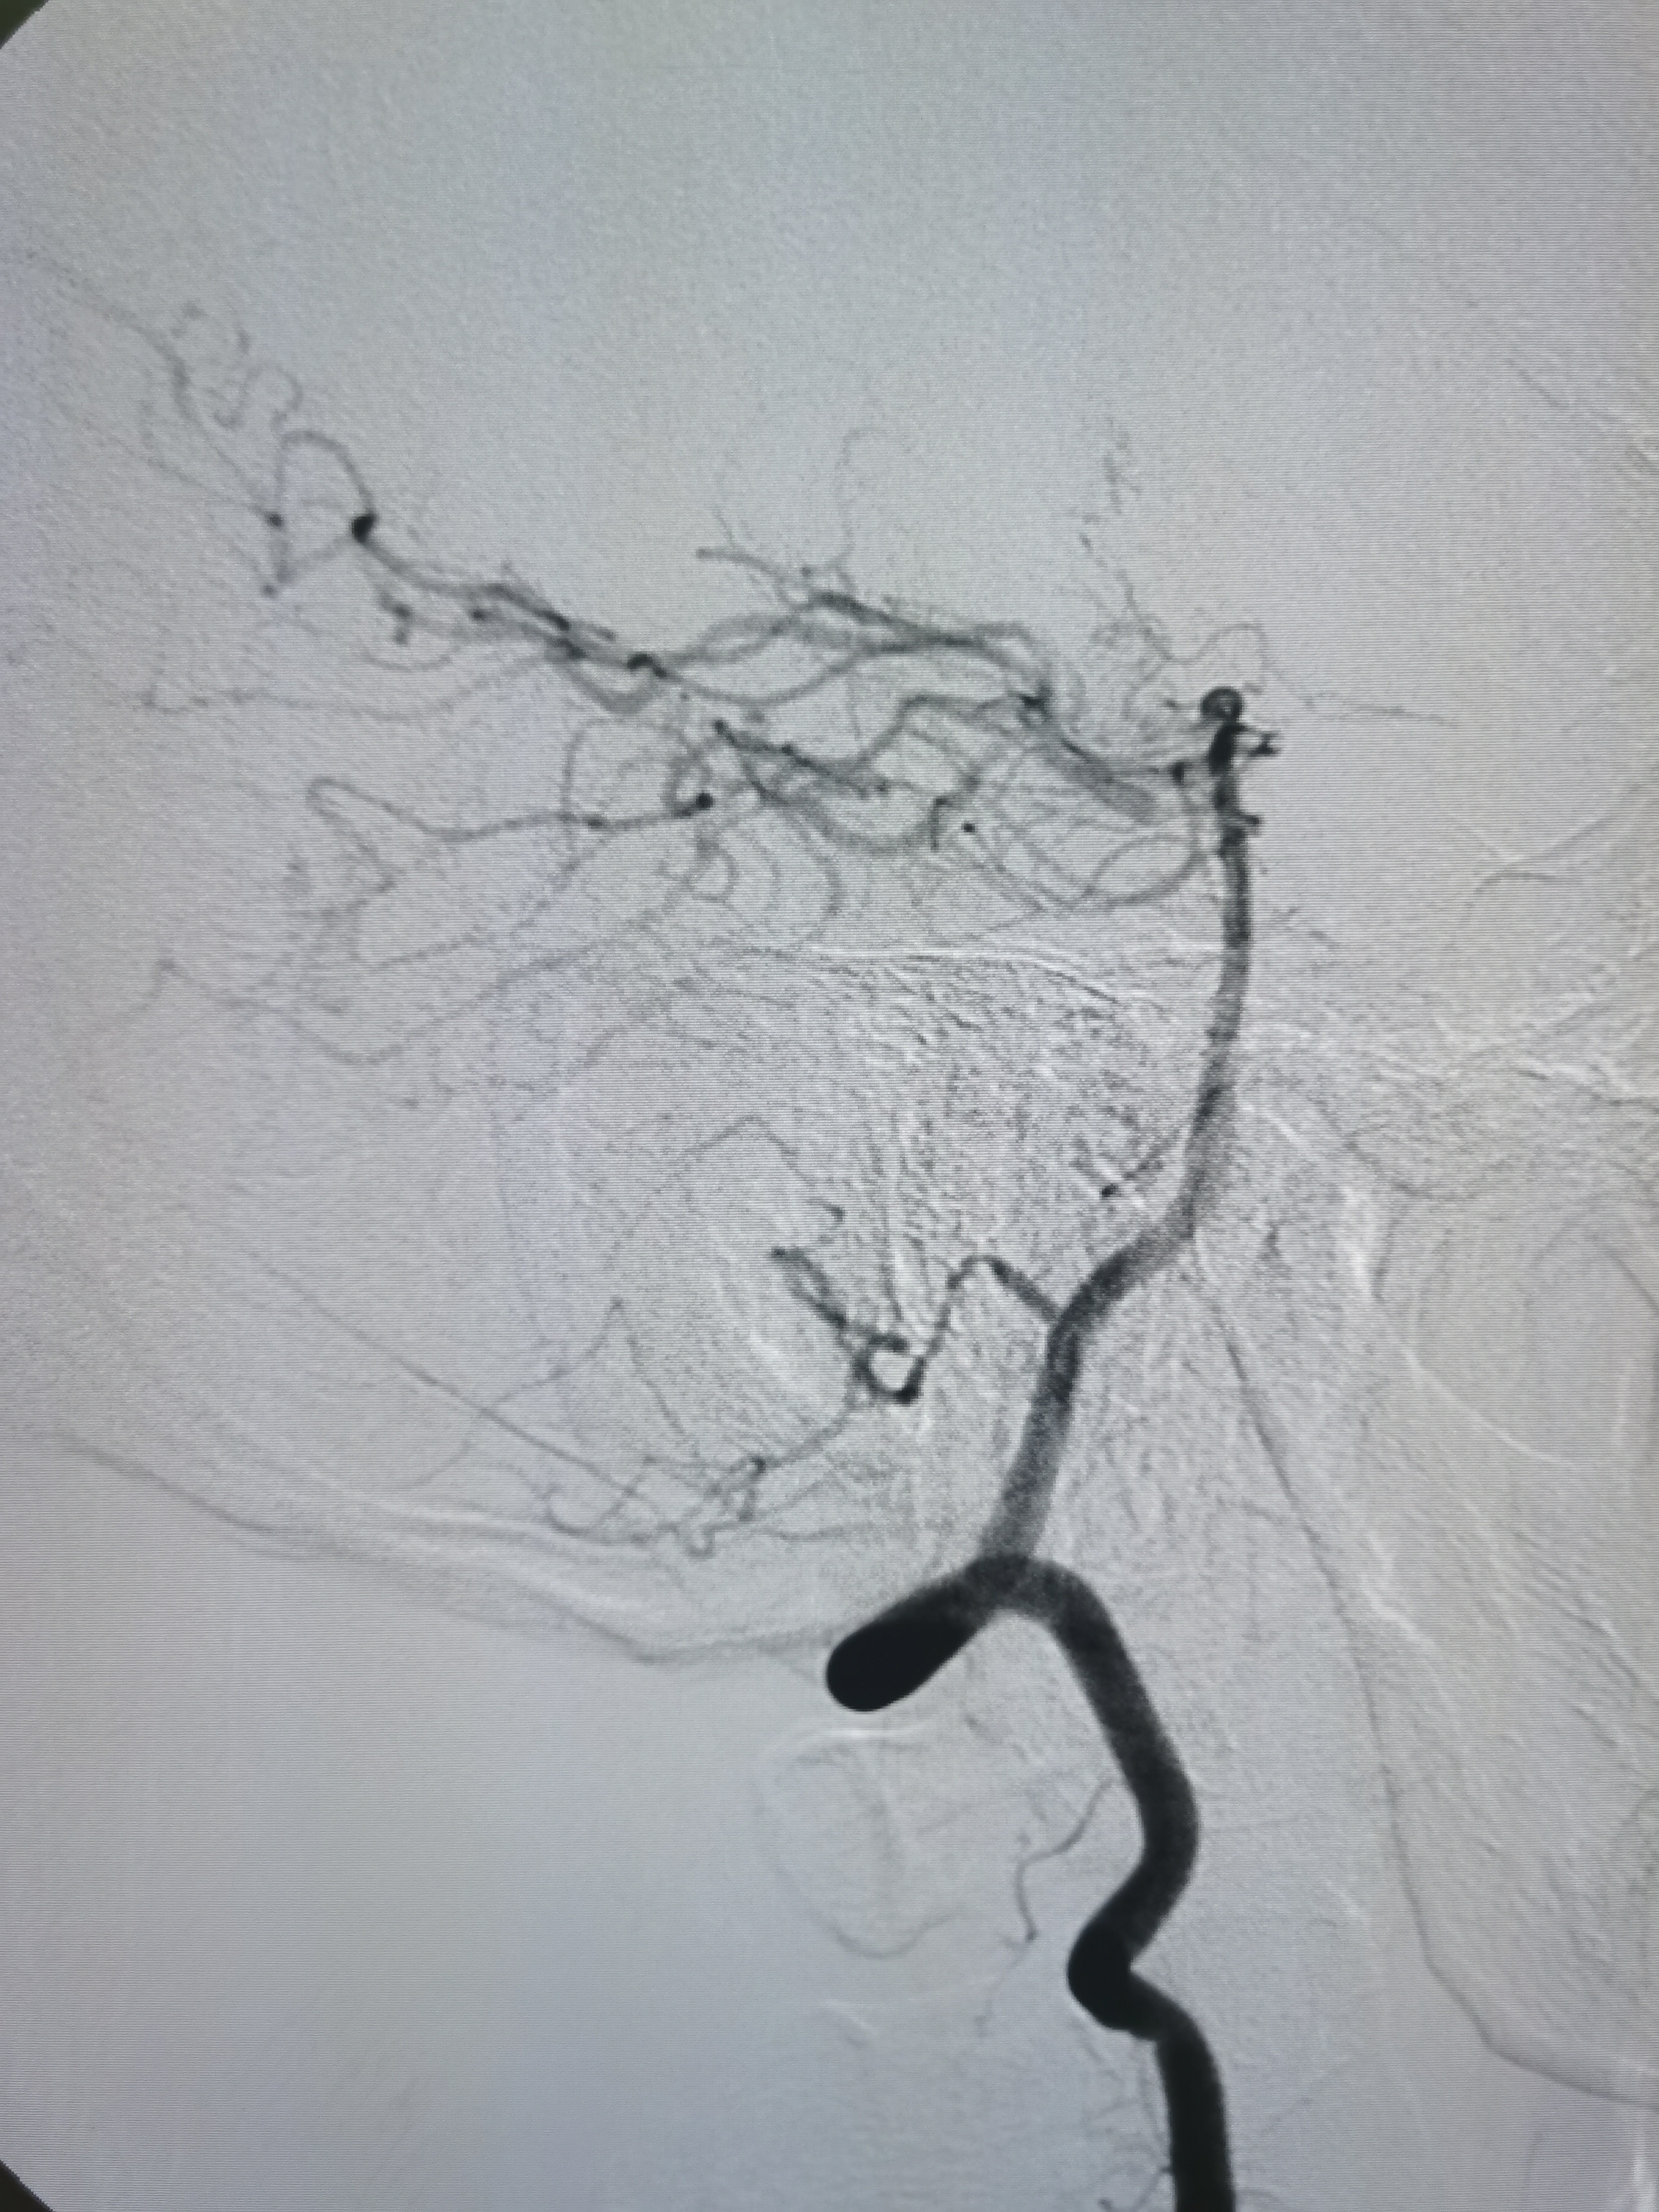

侧位见左侧大脑中动脉闭塞。

晚期可见左侧大脑中动脉返流。

正位见左侧大脑中动脉闭塞。

动脉晚期可见左侧大脑中动脉M2段返流。

造影分析:

患者左侧大脑中动脉M1起始段闭塞,动脉晚期可见返流至M2显影,考虑新近闭塞,具备介入开通指征,手术风险在于血管夹层,破裂及急性血栓形成,向患者家属详细交代病情后,家属积极要求介入治疗。